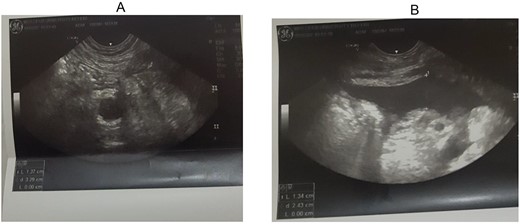

Abdominal ultrasound was done and there was dilated tubular and blind-ended appendix, which has connection cecum. It is not compressible with outer-to-outer wall diameter of 10 mm as shown in Fig. 1A and B. There was mucosal and wall defect at its distal tip and there was adjacent fluid collection localized to right lower quadrant. With this finding, the diagnosis of stump appendicitis with perforation was made.

(A, B) Right lower quadrant ultrasound study showing dilated appendix and right lower quadrant fluid collection.

On the same day, exploratory laparotomy with a lower midline incision was performed under general anesthesia. The operative findings were inflamed stump of appendix (~2 cm) with perforation at its tip with surrounding abscess collection. Rest of the bowel was normal. Completion appendectomy was performed and the postoperative period was uneventful, and on postoperative Day 5, the patient was discharged (Fig. 1A and B).